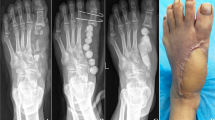

Following a modular design would help in the industrialization of the P&O parts and in the definition of the required TRL that should be met. The prothesis consists of several components1. Figure 4 shows the selected common size of 27 under investigation. The components of the foot can be classified as modular parts. The modular components are like the pyramid metallic adaptor and the bolts. The upper and lower parts of the foot itself are also considered modular products as they can be classified to specific modular sizes. Non modular part is like the socket which connects the pyramid with the amputee remaining part of the leg.

Selected common size of prosthesis foot.

The entire assembly of the prosthetic foot components took place after fabrication, and it went through mechanical testing following ISO22675 guidelines, as detailed in Table 4. Figure 11 illustrates some of the mechanical tests that were applied to the assembled foot. Following the completion of these tests, a thorough inspection was conducted to identify any visual defects, such as delamination, dismounting, or indentation marks resulting from over-tightening. The mechanical tests described in this study adhered to ISO22675 standards and did not involve any experiments on amputees or human subjects.

Mechanical testing of the foot assembly.